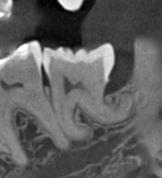

Коли коріння «ховає сюрпризи» - Корені зубів часто мають складну кривизну, гачкоподібні закручення або розгалуження, які на звичайному 2D-знімку накладаються один на одного, створюючи ілюзію прямого каналу. На плоскій картинці неможливо побачити реальний об'єм та напрямок вигину, що критично важливо при видаленні «зубів мудрості» або ендодонтичному лікуванні. КТ MyRay дає змогу лікарю заздалегідь побачити 3D-геометрію кожного кореня, оцінити його близькість до нижньощелепного нерва чи гайморової пазухи та підібрати правильну тактику роботи. Це мінімізує ризики поломки інструменту в каналі або травмування сусідніх структур, перетворюючи складну хірургію на прогнозовану процедуру.

Часто причиною зубного болю є гайморит, і навпаки — причиною запалення пазух є хворий зуб. На звичайному знімку пазуха виглядає як темна пляма. На КТ ми бачимо стан слизової, наявність кіст або сторонніх тіл (наприклад, залишків пломбувального матеріалу), що критично важливо для правильного діагнозу.